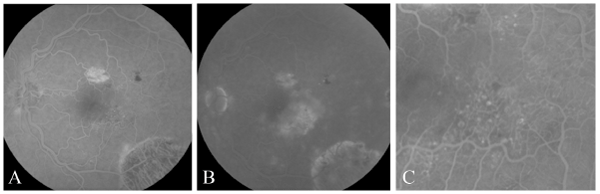

| Figure 2: (A) FA in February 2009 demonstrates telangiectasis and aneurysms in the temporal macula during the early phase. (B) Late leakage is seen on the FA done in February 2009. Magnified view of telangiectasia and aneurysms seen in the macula of panel B. |